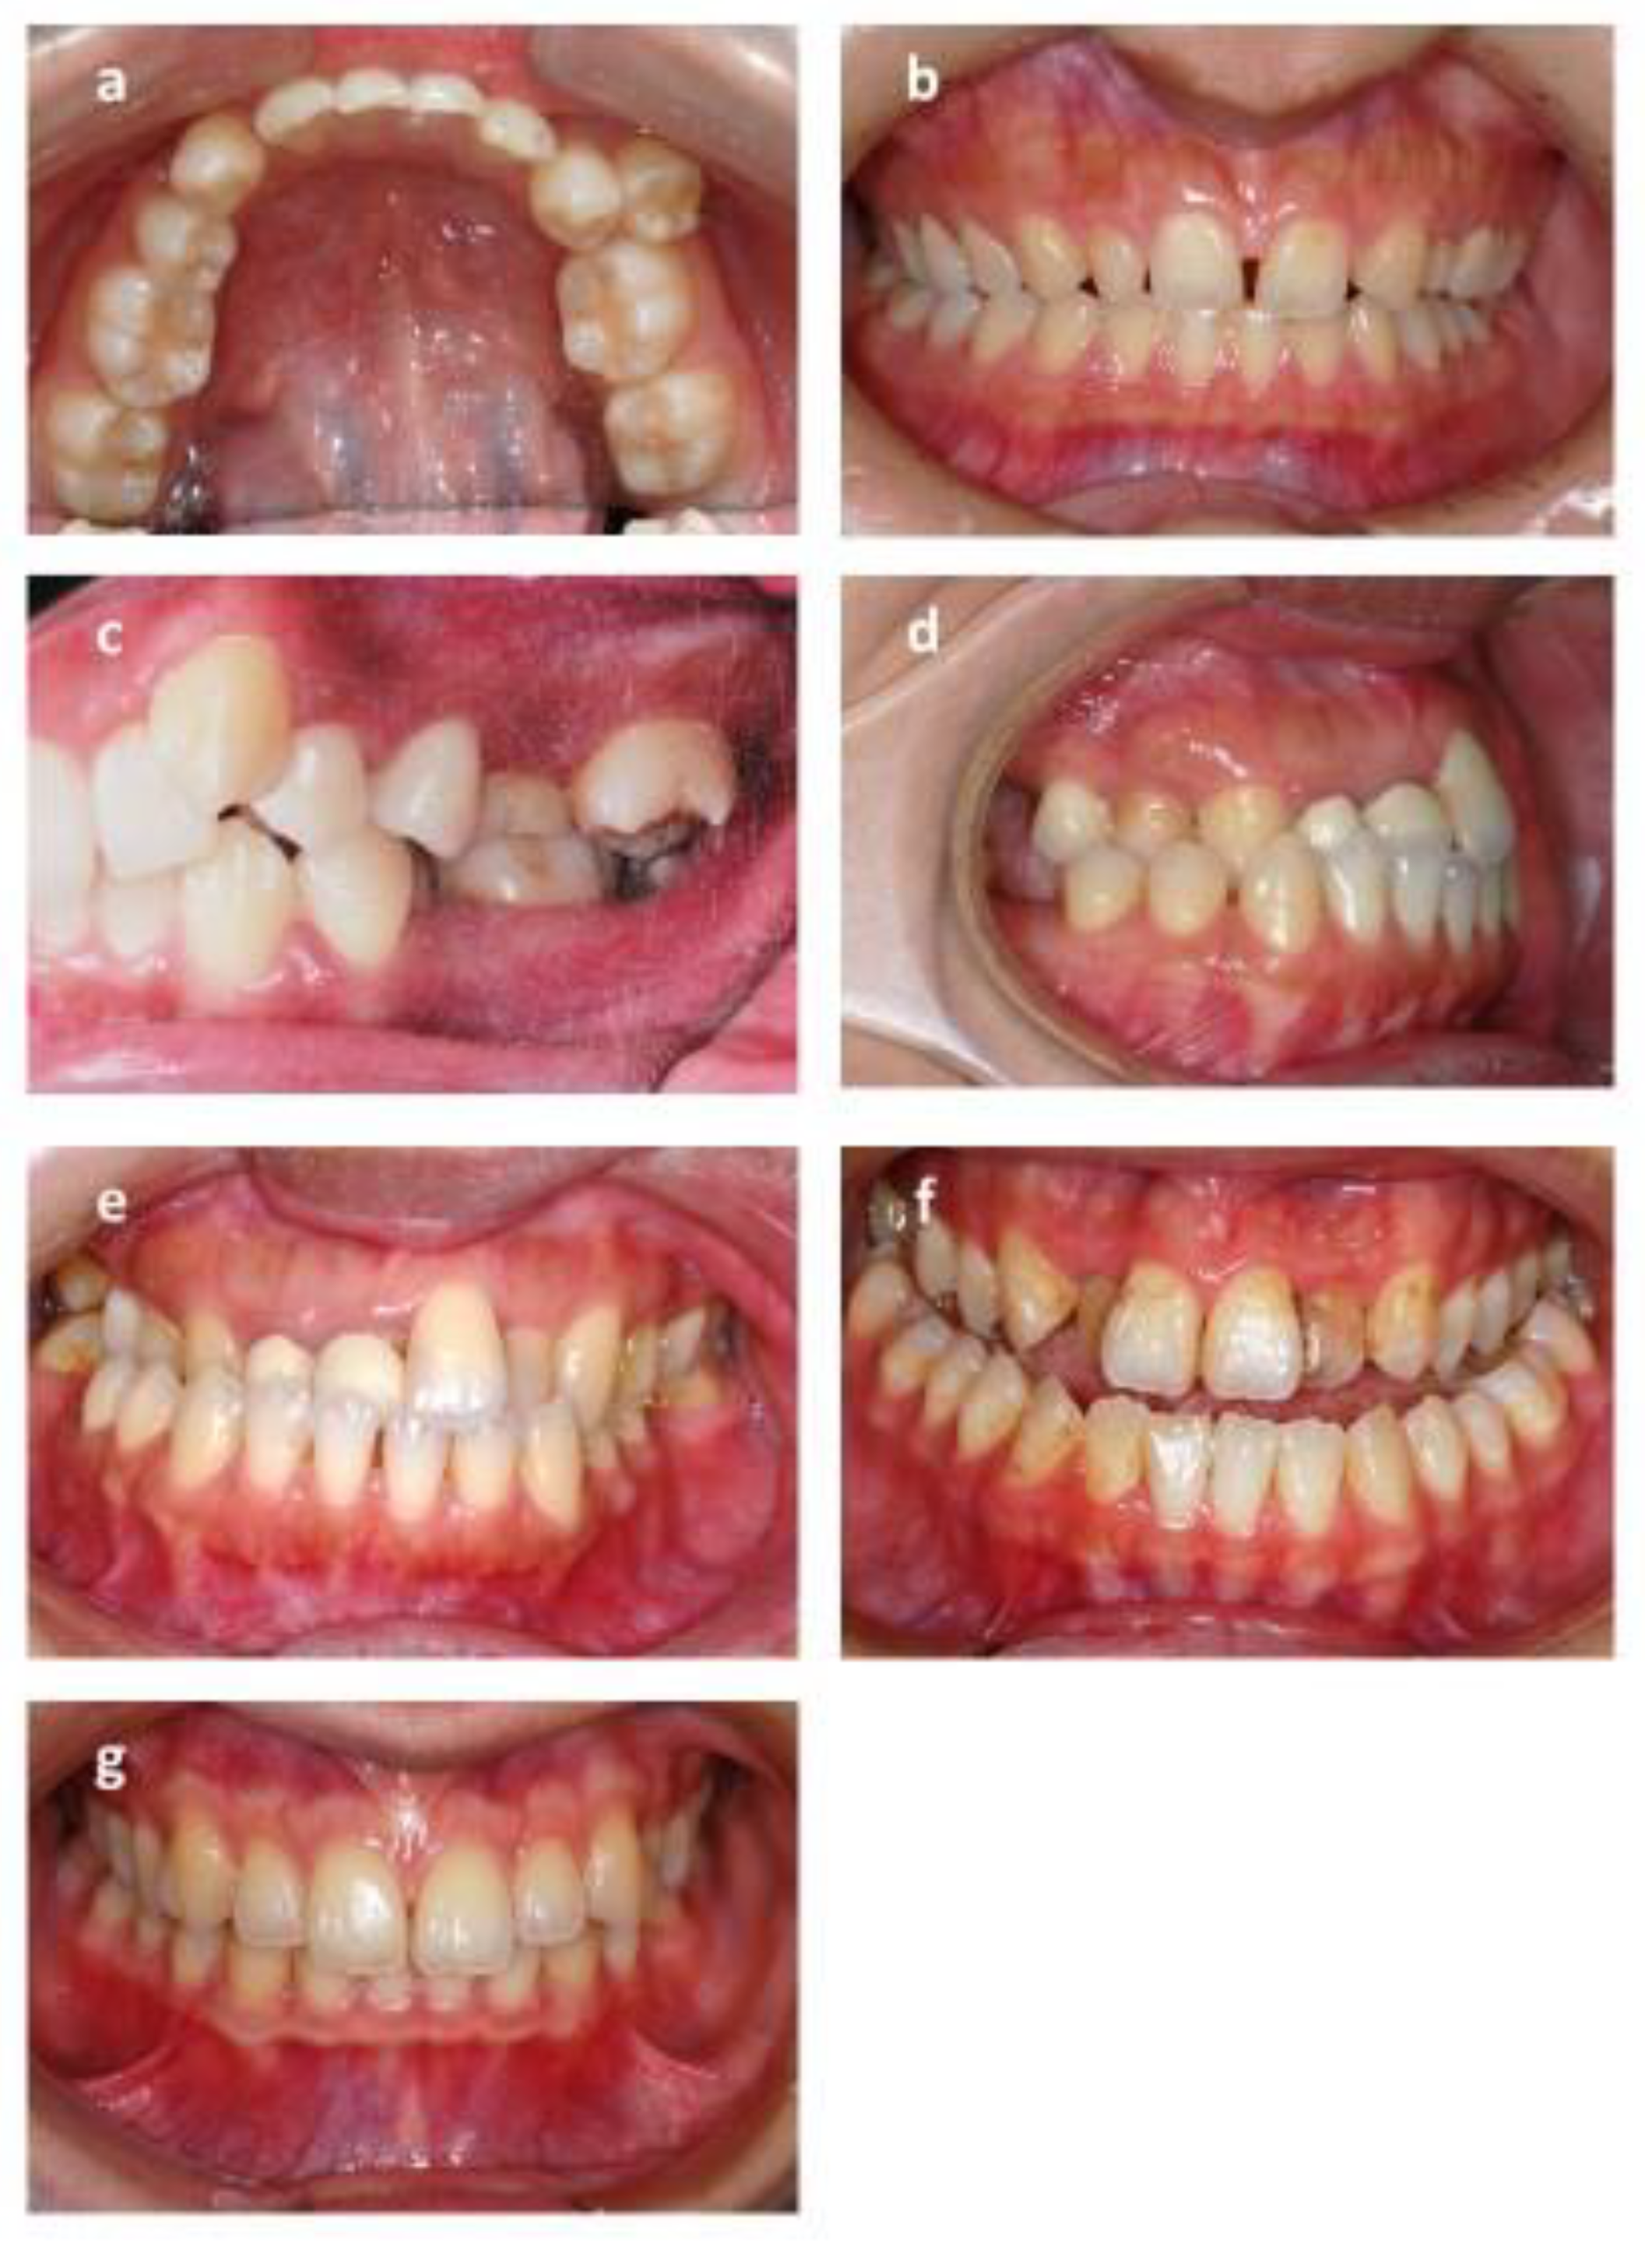

ICON is an index of complexity outcome and need that is used for assessing the orthodontic treatment need (Figure 4). ICON has been proposed as a multipurpose occlusal index, including dental components such as crowding measured with the irregularity index/spacing (sagittal dimension), cross bites (transverse dimension), anterior open bite/overbite (vertical dimension), and sagittal posterior occlusion relationship as well as the esthetic component. The esthetic component comprised 10 color photographs showing dentition in the frontal view graded from 1 (most attractive) to 10 (least attractive). The dental indices were documented as numeric values according to the standard. The final ICON score was divided into malocclusion complexity grades (<29 = easy, 29–50 = mild; 51–63 = moderate, 64–77 = difficult, >77 = very difficult). A cutoff point of 43 was set to mark a definite need for orthodontic treatment [41].

Figure 4. Dental component scale of index of complexity outcome and need (ICON). (a) Crowding: crowding occurs when there is a discrepancy between the space required by teeth and the space available in the jawbone. The irregularity index is used for measurement. (b) Spacing: the opposite of crowding, the space available is larger than space required. (c) Posterior buccal crossbite: buccal cusp of the mandibular dentition occludes lingually to the lingual cusp of the maxillary dentition. (d) Posterior lingual crossbite: buccal cusp of the mandibular dentition occludes buccally to the buccal cusp of the maxillary dentition. (e) Anterior crossbite: maxillary incisors occlude lingually to mandibular incisors. (f) Open bite: there is no vertical overlap between the maxillary and mandibular incisors. (g) Overbite: the vertical overlap of the incisors.